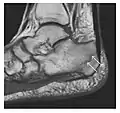

a

b

Figure 10: Calcaneal fatigue fracture in a 30-year-old male runner. Radiographs were normal (not shown). (a) Sagittal T1-weighted and (b) short tau inversion recovery images show a linear hypointensity (arrows) of calcaneal tuberosity within diffuse bone marrow edema, which appears as an ill-defined area of hyperintensity on a fluid sensitive pulse sequence (arrowheads).[1]